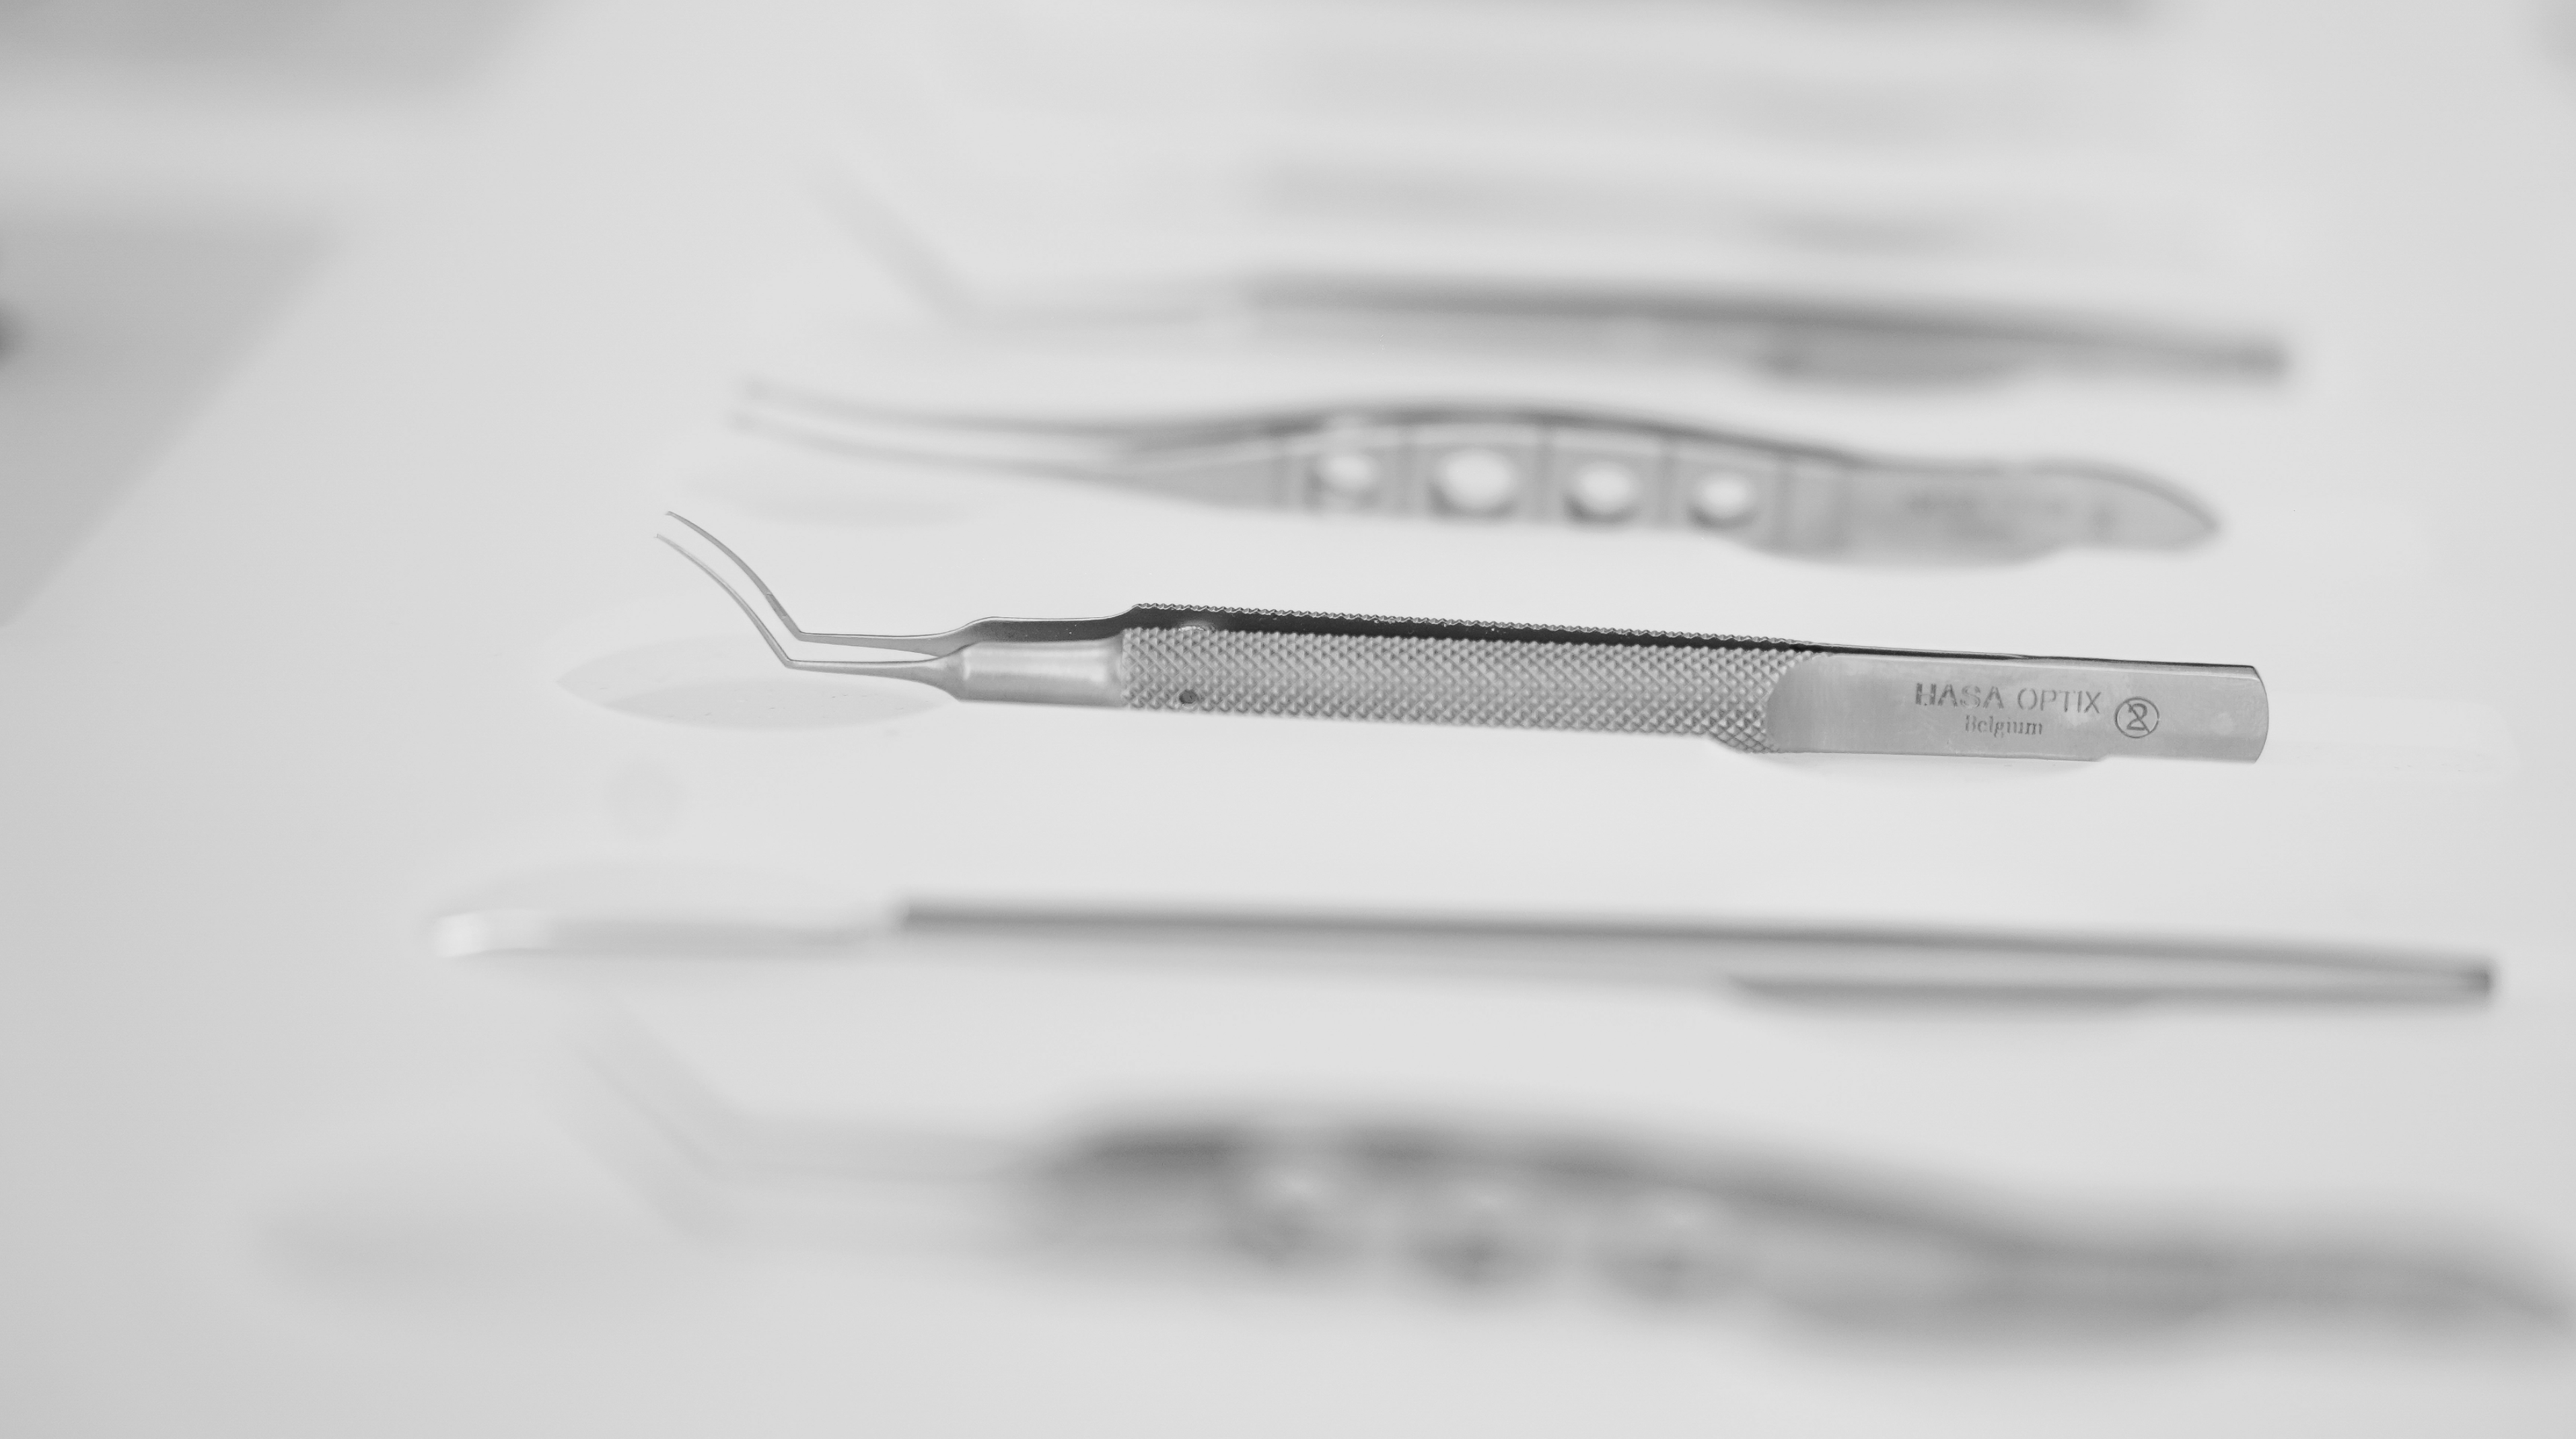

Ophthalmic Surgical Instruments

Wide range of recyclable ophthalmic surgery instruments.